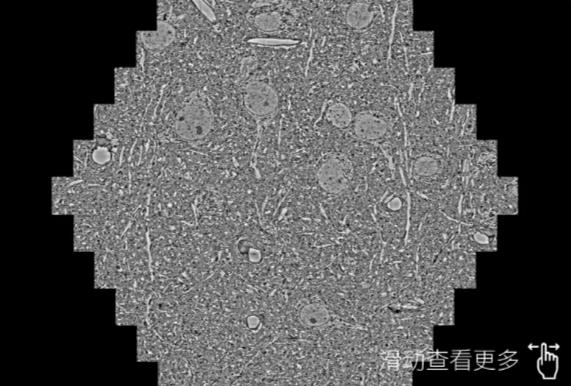

鼠脑切片。左图使用嘉兴蔡司嘉兴扫描电镜MultiSEM706对165μmx143pm面积区域成像,耗时仅需1.5秒。右图为鼠脑切片中30μm区域放大效果。样品由芝加哥大学B.Kasthuri提供。

使用蔡司高速嘉兴扫描电镜MultiSEM对1mm²人脑皮层组织进行高分辨成像,并对其中的各种细胞结构进行三维重构分析。左图展示了2x3mm²组织平面中锥体神经元的三维重构效果。右图显示了局部体积神经元三维重构。图像由哈佛大学chtman实验室提供,渲染图由D. Berger 制作。